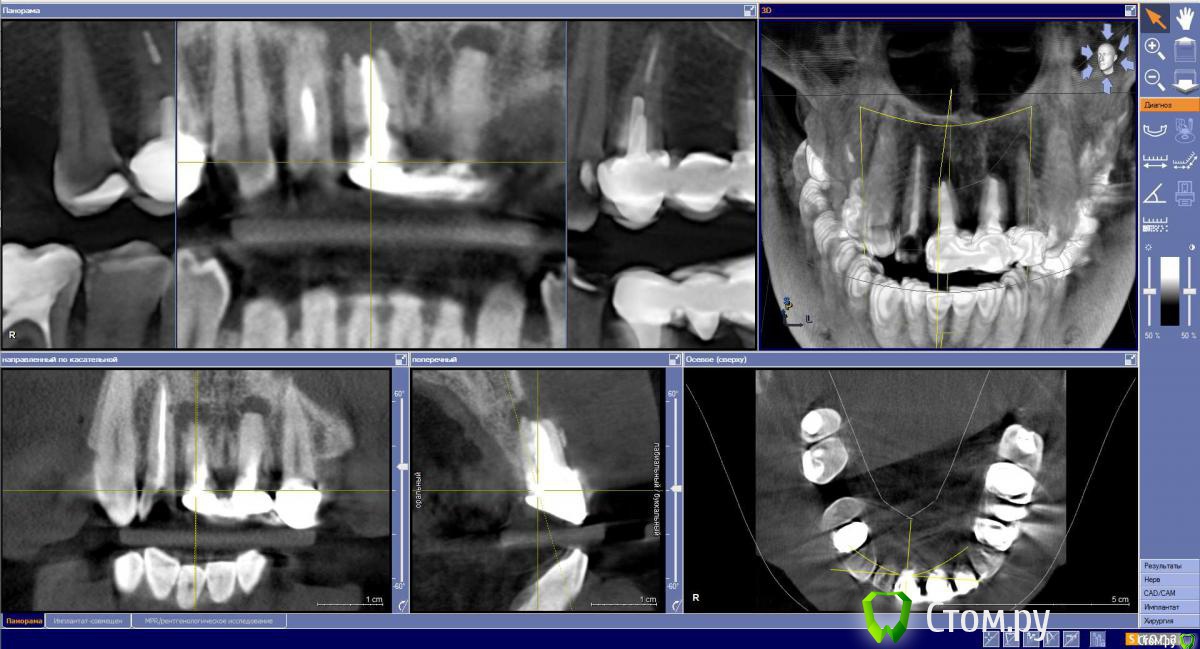

Sergei27 Опубликовано 17 мая, 2015 Поделиться Опубликовано 17 мая, 2015 (изменено) Мне 40 лет 1.1 и 2.1 травма 29 лет назад, повторные кисты после резекции 16 лет назад. 1.2 и 2.2 уже депульпированы и подготовленны под временный мост. Планируемый план лечения:1 день:Удаление 1.1 и 2.1 (была опечатка, исправил)Cerabone 0.5млУстановка импл. NeoBioTech (Ю.Корея)4 день: Слепок и временный мост на двойки.60-180 ? день:Установка постоянных коронок 1.2 1.1 2.1 2.2 Вопрос: Правильно ли выбран план лечения?Предыдущий план предполагал удаление и костную пластику, и после 6 мес имплантацию. Изменено 17 мая, 2015 пользователем Sergei27 Ссылка на комментарий